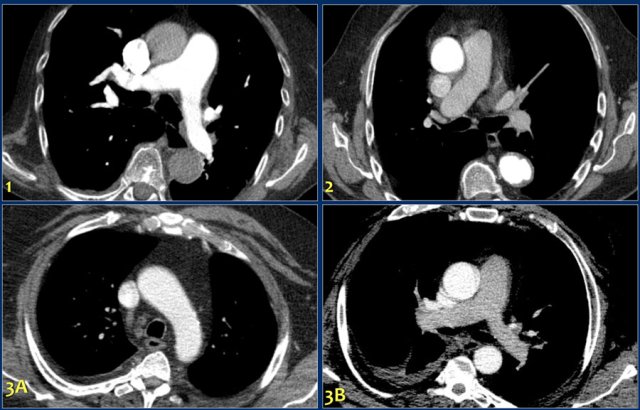

The images demonstrate:

- Optimal enhancement of pulmonary arteries in an old patient with a poor cardiac output.

- Poor enhancement of pulmonary arteries due to late scanning.

- Good enhancement in SVC and aorta in image 3A, but insufficient enhancement of the pulmonary vessels due to TIC in image 3B.